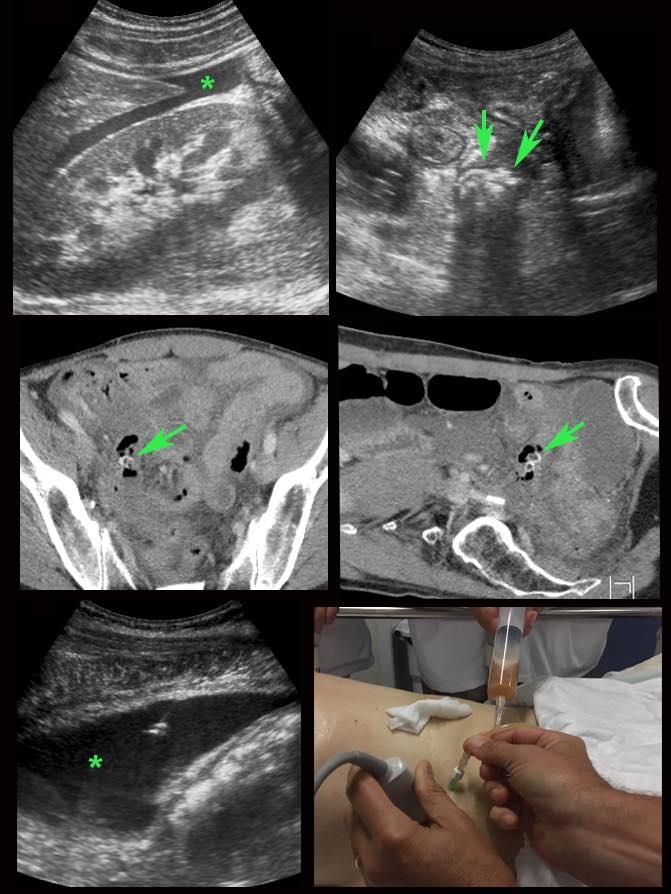

Viêm ruột thừa với sỏi phân trong lòng ruột thừa (mũi tên) được tìm thấy tại vị trí tắc nghẽn (a và v = động mạch và tĩnh mạch chậu).

Ở bệnh nhân này với đau hố chậu phải kéo dài 18 giờ, CT chỉ cho thấy hình ảnh thâm nhiễm mỡ tối thiểu xung quanh ruột thừa 8,5 mm (mũi tên).

Siêu âm với kỹ thuật ép có kiểm soát đã cho thấy rõ ràng mô mỡ viêm tăng âm, không thể ép xẹp (đầu mũi tên) xung quanh ruột thừa.

Ở bệnh nhân này, siêu âm cho thấy lượng lớn mô mỡ viêm (*) và hồi tràng dày thành, biểu hiện quá trình bao bọc thành công tình trạng thủng (sắp xảy ra) của ruột thừa (mũi tên).

Lưu ý sỏi phân vôi hóa (mũi tên trên CT) trong ruột thừa ở mức cao hơn.

Ở người phụ nữ 56 tuổi này với CRP 180, siêu âm phát hiện dịch trong phúc mạc đục (*) và có thể thấy ruột thừa viêm với sỏi phân (mũi tên).

CT xác nhận hai sỏi phân ở hố chậu phải với hình ảnh khí bất thường, nghi ngờ viêm ruột thừa thủng.

Chọc hút dưới hướng dẫn siêu âm xác nhận dịch mủ.

Phẫu thuật cấp cứu phát hiện viêm ruột thừa thủng với nhiễm bẩn mủ bốn góc phần tư ổ bụng.